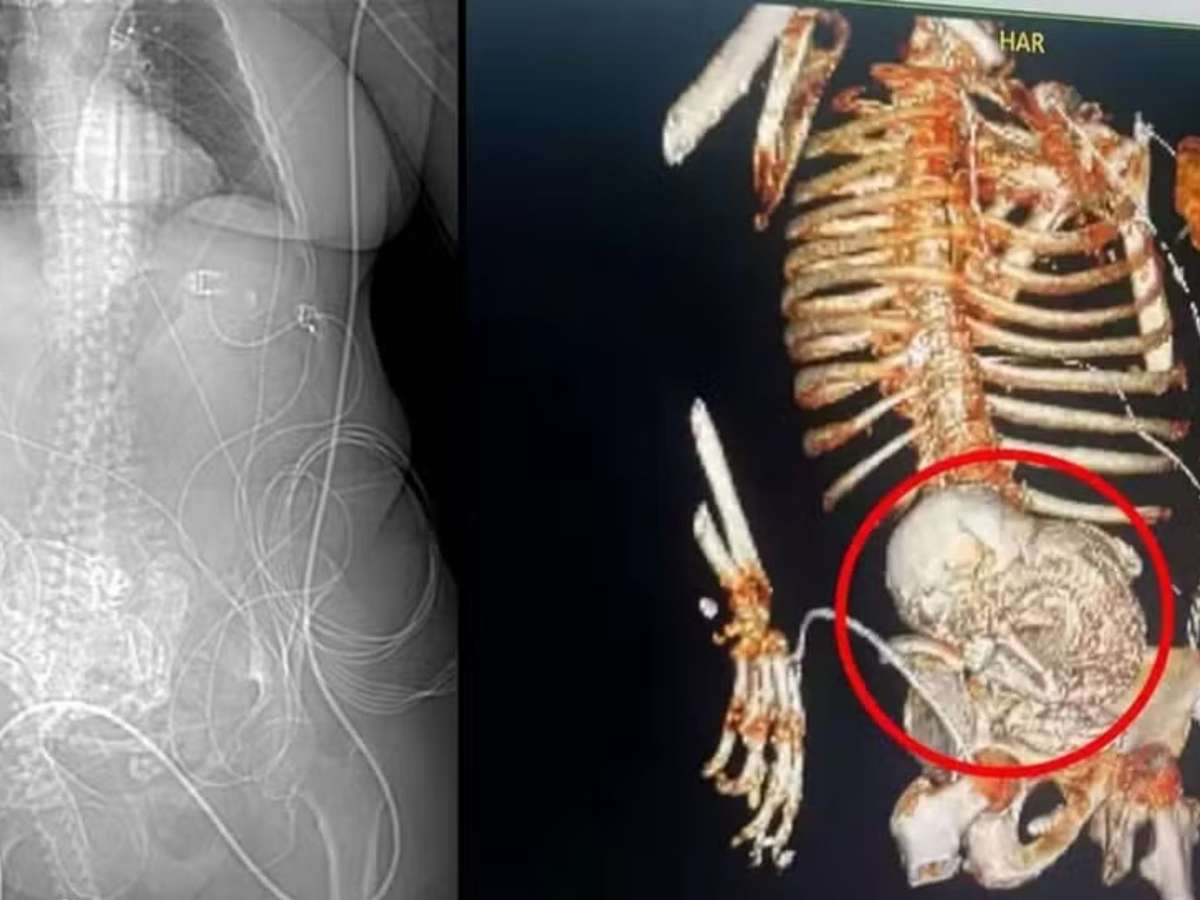

Mulher morre após complicações em cirurgia para retirar "bebê de pedra" do abdômen

Uma mulher indígena, de 81 anos, morreu após sofrer complicações em uma cirurgia para retirar um feto calcificado de seu corpo. Ela deu entrada em um hospital da cidade de Ponta Porã, em Mato Grosso do Sul, com dores abdominais. Com exames, os médicos detectaram um caso raro de litopedia, quando um organismo cobre outro, em seu interior, com tecido ósseo para evitar infecções.

Os profissionais deduziram que se tratava de uma gravidez ectópica, quando acontece fora do útero, e que a mulher carregava o feto há mais de 50 anos. Após a cirurgia, em 14 de março, ela foi direcionada para a UTI do hospital, mas não resistiu a uma infecção generalizada causada por uma infecção urinária. Segundo o secretário de Saúde de Ponta Porã, Patrick Dezir, ela morava em um assentamento indígena na cidade de Aral Moreira e já tratava um quadro de dores abdominais. Após o agravamento da condição, ela foi transferida para o hospital a cerca de 80 km.

"Quando ocorre a gravidez, ela deve estar dentro do útero, mas em alguma situações a gravidez pode ocorrer fora. Aquele bebê não deu clínica, a paciente não teve uma dor aguda e não teve um grande sangramento e esse diagnóstico passa desapercebido e o tempo vai se encarregar daquele corpo estranho que ficou dentro do abdômen da mulher", explicou o ginecologista e mastologista João Bosco Borges, ao g1.

Como pode não ser detectado imediatamente, o corpo calcificado tem a possibilidade de resultar em complicações futuras. Borges afirma que esta condição é mais comum em países de terceiro mundo, onde a fiscalização e prevenção são mais precárias. "Isso mostra que em algum momento essa mulher teve um quadro doloroso, mas faltou o diagnóstico de que ela tinha uma gravidez abdominal ou ectópica que se rompeu e aquele bebê caiu no abdômen", completa.